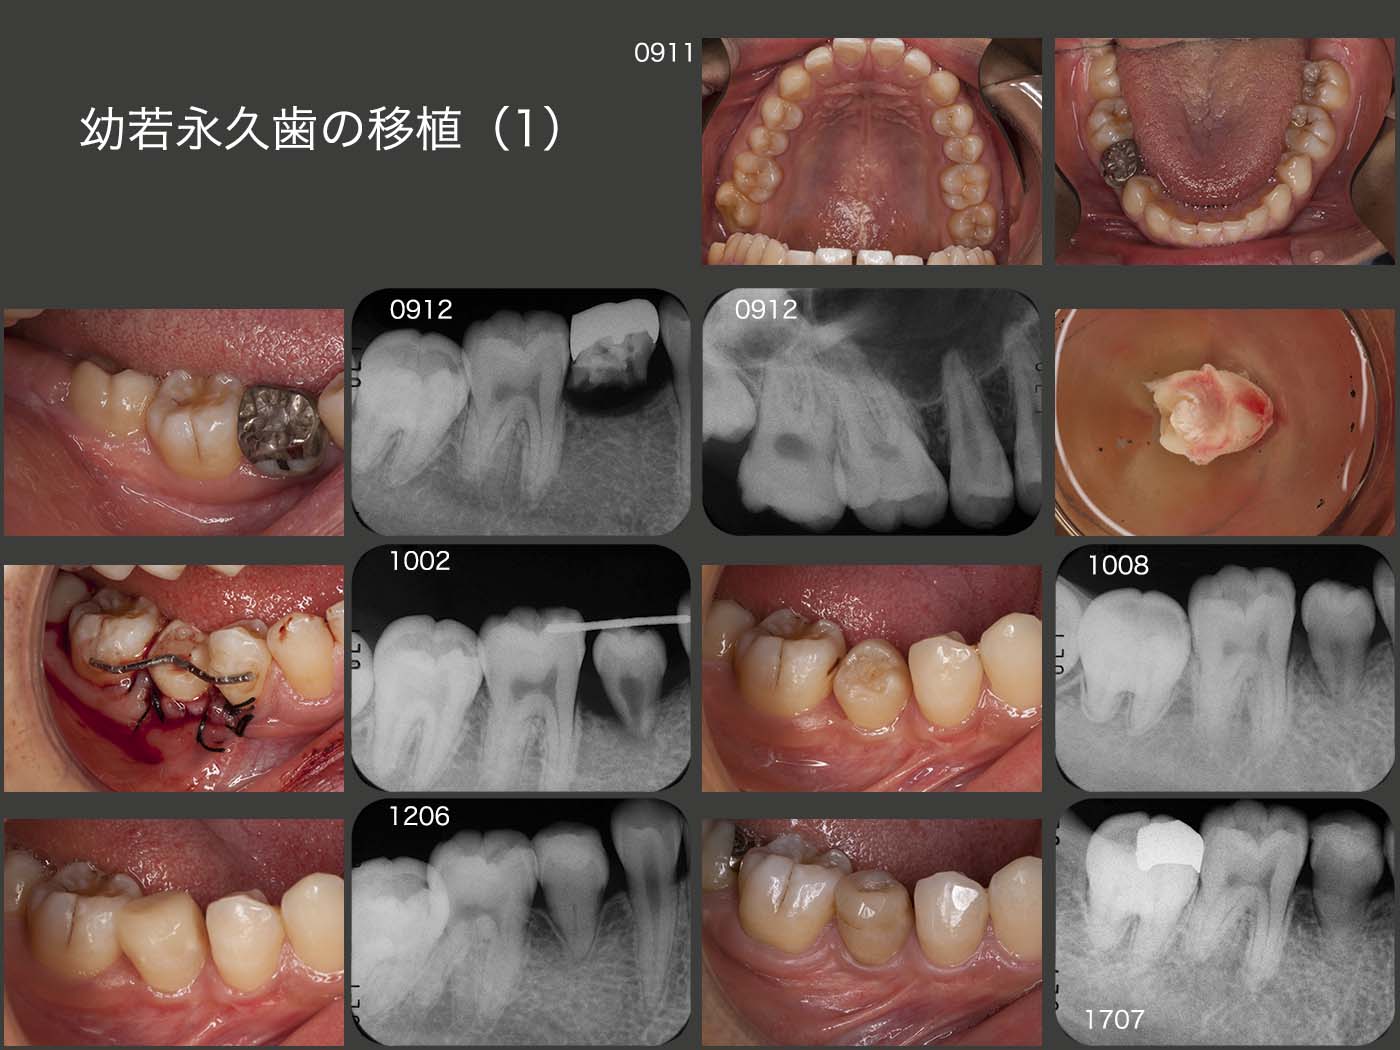

1. 幼若永久歯の移植(1)

2001年初診,当時10歳男の子.今回は09年11月再初診,18歳.右下第2乳臼歯の動揺で来院.まず乳歯を抜歯した.全くの健全歯である隣在歯を形成してブリッジを装着するのではなく,移植するドナー歯がないか良く観察することが大切である.この症例では,デンタルX線写真から右上8が存在したので,この歯を移植することにした.根尖孔の幅が1mm以上ある幼若永久歯の移植の場合,歯髄が保存され,歯根が成長し,根尖孔が閉鎖することが知られている.

10年2月に移植を行った.半年後の8月には歯槽骨内の歯根が長くなっていることが確認できる.なお,9月にコンポジットレジンを用いて,咬合を回復した.近心は歯の形態が悪くなるので,特にコンタクトの回復を行わなかった.

12年6月および17年7月の経過を示すが,歯髄腔がさらに消失していくがみてとれる.歯の変色は気になるが,電気歯髄反応はプラスであることから歯髄は生きていると思われる.

生体の治癒力に大変驚かされた症例である.これには,インプラントはかなわない.